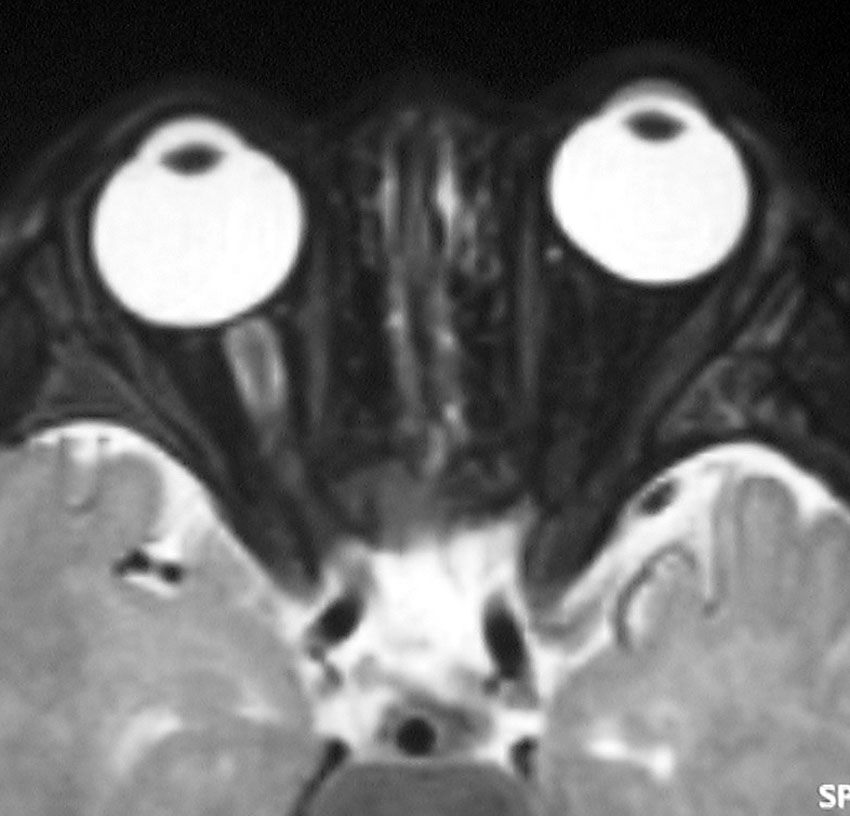

whole optic pathway pilocytic astrocytomaとは

両側の眼窩内視神経から視交叉、視索,外側膝状体,内包後脚,視放線近位部までが腫瘍化しています。FLAIRで高信号で,不規則にガドリニウム増強されます。これを手術摘出したり生検したりしても無駄です。放射線治療は不可能であり治療方法は化学療法のみです。

この子はCDDP/VCRの化学療法から開始して12年になりますが,今は無治療でわずかな視力ですが学校に通っています。優等生です。自然退縮を見ていますが,今後も変化する可能性はすこし残しています。